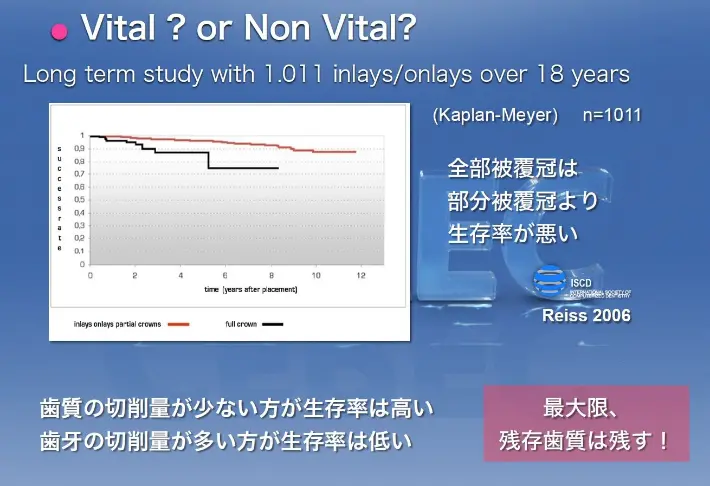

また、論文では小さな被せ(部分被覆管)は大きな被せ(全部被覆管)よりも長持ちすることが証明されています。

保険の樹脂は歯と密着する面が少ないため大きな被せにする必要がある一方、セラミックは歯と密着する面が大きく小さな被せでも固定できます。その点でも、セラミックの被せ物は優れていると言えるでしょう。